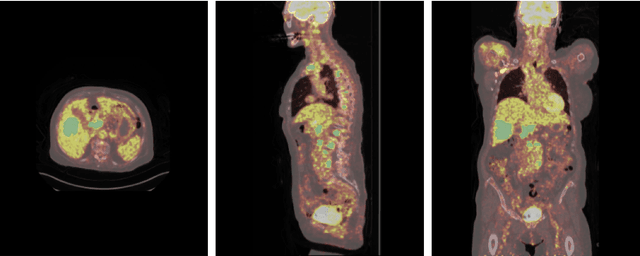

Abstract:Early cancer detection is crucial for improving patient outcomes, and 18F FDG PET/CT imaging plays a vital role by combining metabolic and anatomical information. Accurate lesion detection remains challenging due to the need to identify multiple lesions of varying sizes. In this study, we investigate the effect of adding anatomy prior information to deep learning-based lesion detection models. In particular, we add organ segmentation masks from the TotalSegmentator tool as auxiliary inputs to provide anatomical context to nnDetection, which is the state-of-the-art for lesion detection, and Swin Transformer. The latter is trained in two stages that combine self-supervised pre-training and supervised fine-tuning. The method is tested in the AutoPET and Karolinska lymphoma datasets. The results indicate that the inclusion of anatomical priors substantially improves the detection performance within the nnDetection framework, while it has almost no impact on the performance of the vision transformer. Moreover, we observe that Swin Transformer does not offer clear advantages over conventional convolutional neural network (CNN) encoders used in nnDetection. These findings highlight the critical role of the anatomical context in cancer lesion detection, especially in CNN-based models.